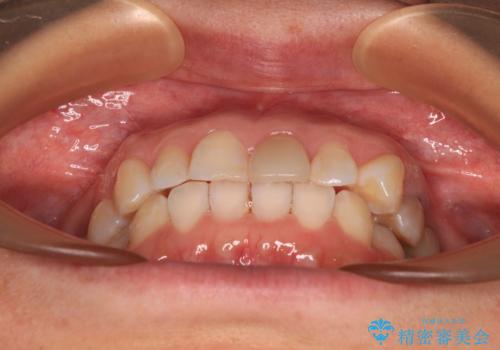

- 上下前歯のデコボコを気にして来院された患者様です。

カウンセリングにて詳しく話を聞いたところ、一番気になっているのは下顎前歯の叢生であり、上顎犬歯はあまり気になっていないとのことでした。

矯正治療は、歯の後戻りを抑制するために、治療終了後も保定装置をしっかりと使用していただくことが必須であるため、気になっている下顎だけを整えることで、その負担を半減できると考え、下顎のみの部分矯正として治療を行うこととしました。

装置としては、叢生の程度が強くなかったため、インビザラインの廉価版であるモデレート・パッケージを使用することとしました。

当院では治療前の歯列が整っていない限り、下顎前歯の舌側をワイヤーで固定するようにしています。下顎のみの部分矯正としたことで、マウスピース保定の負担を軽減することができました。

上顎は、失活して歯の色が変色しているため、将来的に補綴治療で自然な口元に仕上げていきたいとのことでした。